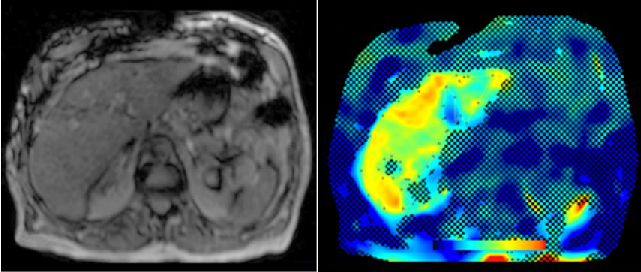

Abdominal MR Imaging

Michaela Plaikner, Benjamin Henninger, Christian Kremser

Morphological and functional MRI in all-organ systems development of novel MRI applications and MR sequences. Examples of research projects: fat, iron or combined disease; influence of iron on the evaluation of liver fat.

a) MRI for the evaluation of diffuse liver disease:

evaluation of different MRI methods (relaxometry, chemical shift imaging, multi-echo approach, Dixon screening), in order to detect diffuse liver disease (fat, iron or combined disease); influence of iron on the evaluation of liver fat.

b) MR-Elastography (MRE)

MRE is increasingly used in hepatic MRI to detect and classify fibrosis in the early stages before morphological changes have occurred. In our department, MRE is already integrated into the routine hepatic MRI protocol and used for various research projects.